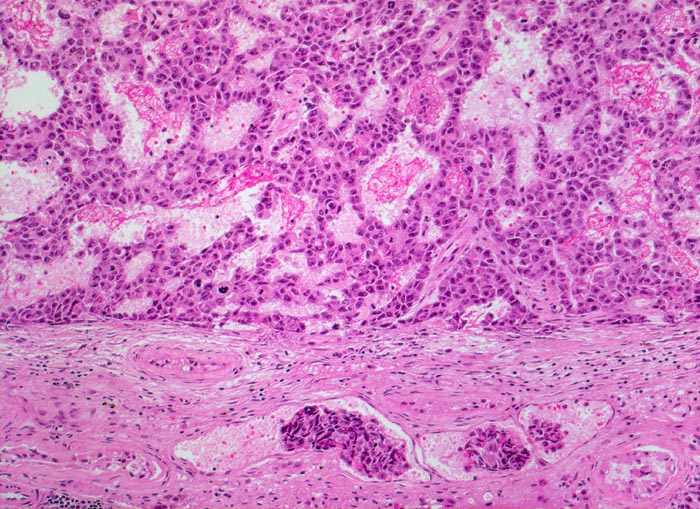

Histologisch bilden die Tumorzellen solide Zellplatten, Drüsen oder papilläre Strukturen mit Einblutungen und Nekrosen. Die Tumorzellen sind polygonal, kubisch oder zylindrisch, haben reichlich Zytoplasma und unscharfe Zellgrenzen. Die grossen Kerne haben grob verklumptes Chromatin und enthalten oft mehrere sehr grosse unregelmässige Nukleolen. Gefässeinbrüche und eine testikuläre intratubuläre Neoplasie sind in der Tumorumgebung häufig nachweisbar

• Polymorphe Tumorzellen bilden miteinander anastomosierende Stränge, solide Zellplatten, glanduläre und kribriforme Strukturen.

• Tumornekrosen.

• Gefässeinbrüche in peritumoralen Gefässen.